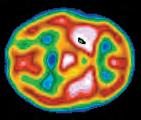

Differenze nell’attivazione cerebrale

Le persone con schizofrenia tendono ad avere prestazioni ridotte nei test neuropsicologici sensibili alle lesioni corticali frontali. Queste scoperte hanno sollevato la possibilità che la corteccia prefrontale possa essere compromessa nella schizofrenia. Le prime indagini, compiute utilizzando la PET, indicano che i pazienti con schizofrenia mostravano una minore attività metabolica nei lobi frontali rispetto ai lobi posteriori, mentre i soggetti di controllo avevano un’uguale attivazione della corteccia frontale e posteriore (M.S. Buchsbaum et al., 1984). I neuroni della corteccia frontale di persone con schizofrenia presentano dendriti con una ridotta densità di spine sinaptiche rispetto ai controlli (Forrest et al., 2018), che può contribuire a una corteccia frontale meno attiva. Queste e altre osservazioni hanno innescato un interesse rispetto al ruolo dei lobi frontali nella schizofrenia (Minzenberg et al., 2009; Penadés et al., 2017). In gemelli identici discordanti, si os-

servano un ridotto flusso sanguigno e cambiamenti associati nella materia grigia solo nel gemello con schizofrenia (T.D. Cannon et al., 2002). Un aumento dell’attività della corteccia frontale è associato con i farmaci che alleviano i sintomi della schizofrenia (Vogel et al., 2016). Infatti, alcune delle scoperte più rivoluzionarie relative alla schizofrenia non vengono da studi su differenze strutturali o funzionali, bensì dalla scoperta di farmaci antipsicotici.